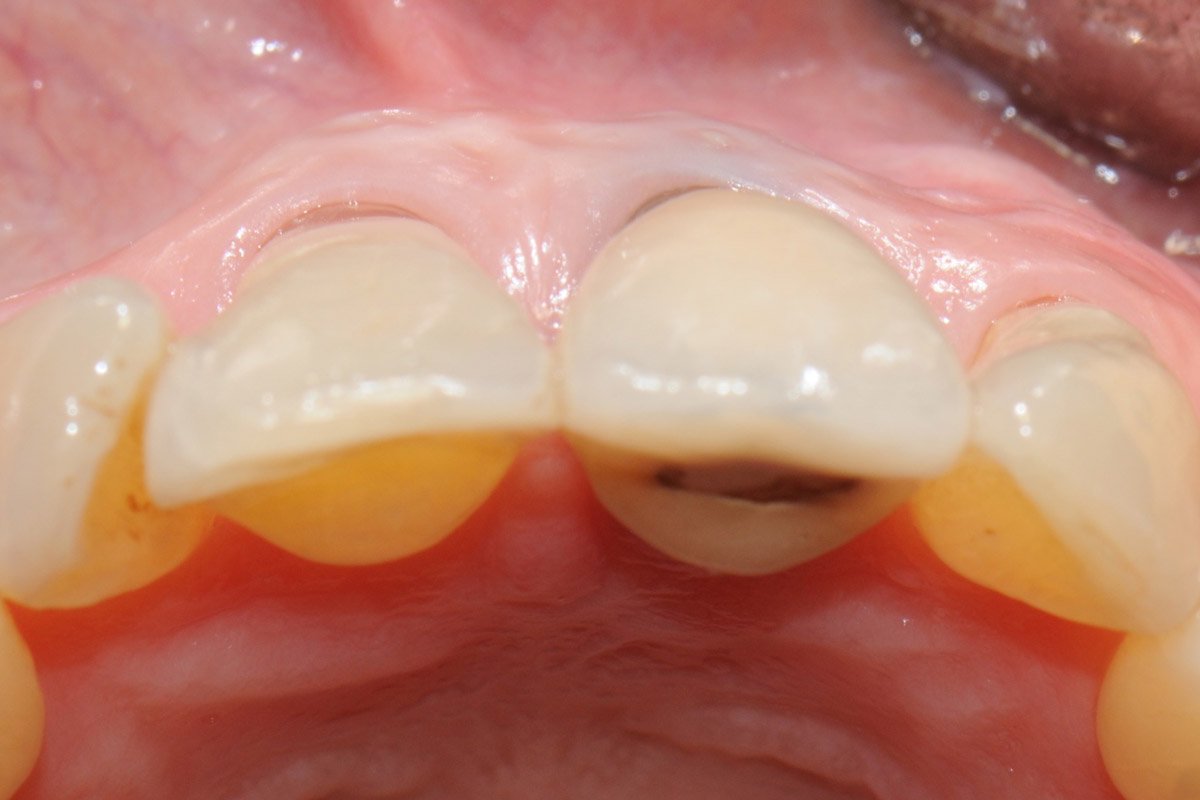

1/18 - Initial clinical situation showing strongly compromised tooth 21Tooth extraction and socket sealing with mucoderm® - Dr. A. Rossi

Initial clinical situation showing strongly compromised tooth 21